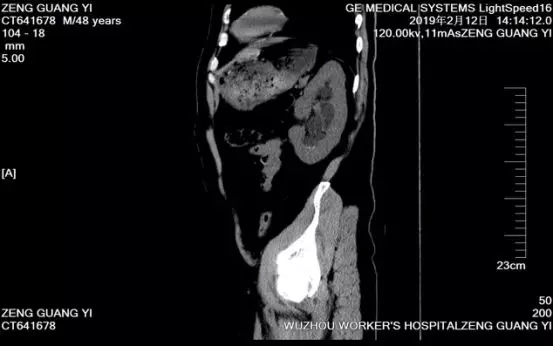

入院后,科室认真研判病情,认为左肾结石大而复杂,患者有腹部手术史,体外震波碎石病史,应用左侧输尿管软镜钬激光碎石不单创伤极小甚至无出血,而且可以一次性解除患者困扰已久的结石病患。手术历时约40分钟,顺利粉碎患者体内结石并取出体外,术后第二日患者便康复出院。出院前,医生还按照结石成分分析结果为他今后防治结石复发提供建议。

(图为曾先生术后复查CT片,矢状面已无结石残留。)